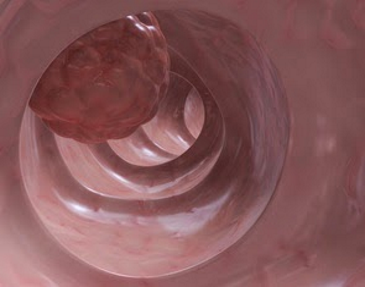

Cáncer

El cáncer de colon tiene actualmente una alta frecuencia y en estados avanzados tiene un pronóstico desfavorable, es por ello, que se requiere de un diagnóstico y tratamiento oportuno con la finalidad de obtener los mejores resultados quirúrgicos y la mayor sobrevida para el paciente. Es por ello que se ofrece un manejo integral mediante un diagnóstico temprano por Colonoscopía y manejo quirúrgico seguro, adecuado y oportuno para el paciente.